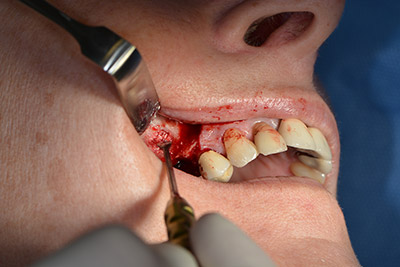

Acto seguido, se coloca el implante y se estructura el hueso. Dado el tamaño del aumento, en el caso que nos ocupa se utilizó hueso autógeno, que había surgido como virutas de fresado en el implante 16 y en la fenestración 14 y se había recogido con un colector óseo, y se combinó con material de reemplazo óseo.

Una membrana reabsorbible formó la barrera en sentido bucal y cubrió el aumento. Por último se procedió a la sutura de modo que no penetrara saliva (figuras 15 a 19).